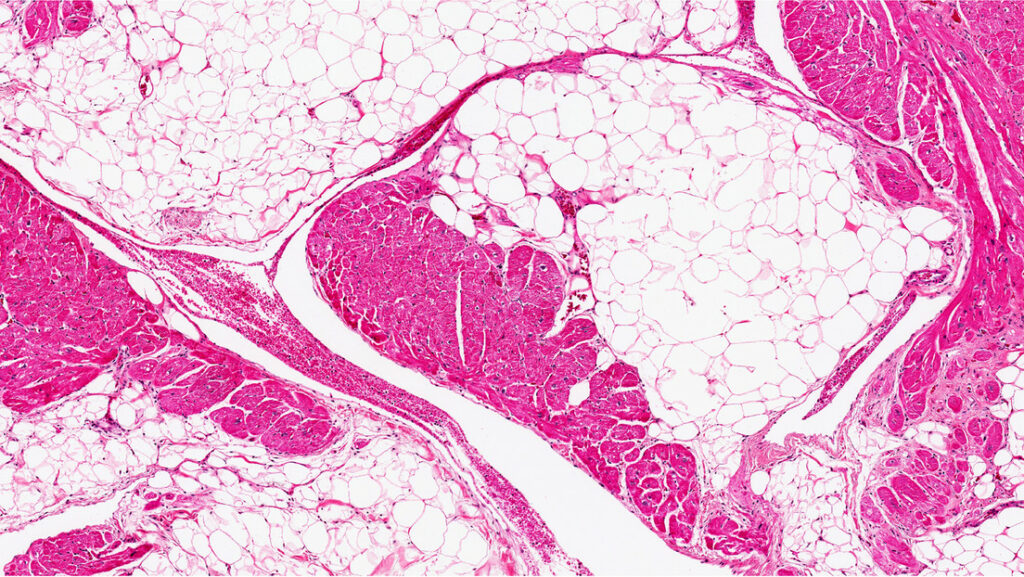

Lo más importante es que el primer grupo perdió grasa visceral, la más peligrosa porque se acumula en la cavidad abdominal, alrededor de los órganos principales. Estos ratones también mostraron un aumento en los niveles de insulina y glucosa en sangre.

En cambio, los investigadores descubrieron que la TSLP estimulaba el sistema inmunológico para liberar lípidos a través de las glándulas sebáceas, productoras de sudor aceitoso en la piel.

Para probar la teoría, los investigadores afeitaron los ratones tratados con TSLP y luego extrajeron los aceites de su pelaje. Descubrieron que la hipótesis de Kambayashi era correcta: el pelaje brillante contenía lípidos específicos del sebo.

Esto confirmó que la liberación de aceites a través de la piel resultó responsable de la pérdida de grasa, inducida por TSLP.